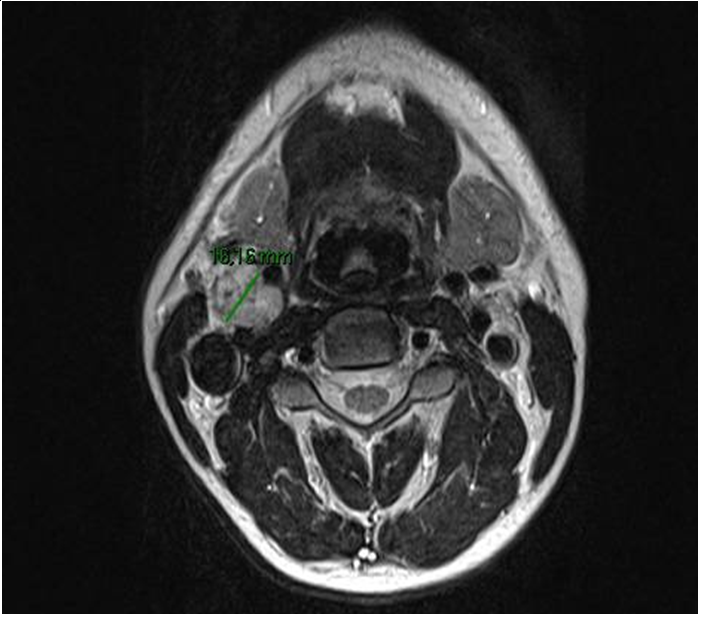

A 31-years old caucasian man came to the neurology emergency department because of the sudden onset of right-sided palsy with sluttered speech. He reported no headache, dizziness or convulsions. After the initial workup, he was admitted to the neurology department. MRI showed subacute ischemic stroke in the posterior part od left insula and operculum. 3D- TOF MR angiography showed occlusion of one of the smaller branches in M2/M3 segment. We performed a doppler ultrasound of carotid and vertebral arteries that indicated vascularized parenchymal structure between ACI and ACE on the right side (Figure 1). Because of that, we did MRI of the neck that verified the inhomogenic structure at the bifurcation of carotid arteries od the right side, dimensions 2,6X1,8X1,9cm that resembles paraganglioma (Figure 2).

Figure 1 Ultrasound of the neck- tansversal plane. Arrows are marking internal carotid artery, external carotid artery and paraganglioma.